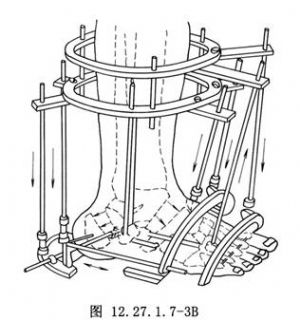

(2)“V”形截骨術:用以改變後足、中足和前足三者之間的位置關係。截骨部位一是在距下關節後方穿越跟骨體部;二是經由跗骨竇穿越距骨頸部和跟骨前部(圖12.27.1.7-3B)。此截骨術的前提條件也是距下關節僵硬。通過截骨術可矯正足前部和後部對於足中部、小腿和地面的成角和旋轉畸形,即矯正其內翻、外翻、內收、旋後和旋前畸形。

(2)V形截骨術:用以改變後足、中足和前足三者之間的位置關係。截骨部位一是在距下關節後方穿越跟骨體部;二是經由跗骨竇穿越距骨頸部和跟骨前部(圖3.19.1.4-6)。此截骨術的前提條件也是距下關節僵硬。通過截骨術可矯正足前部和後部對於足中部、小腿和地面的成角和旋轉畸形,即矯正其內翻、外翻、內收、旋後和旋前畸形。